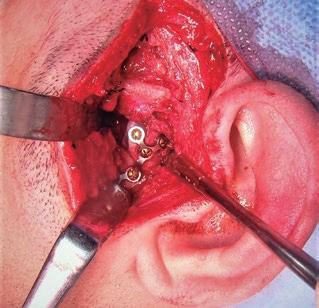

SFIG. 2, a-i. Fractura subcondilar izquierda baja consolidada en una posición incorrecta y que requirió una nueva cirugía abierta correctora a través de una incisión preauricular con descarga. a) Detalle de la OPG con el eje mayor normal condilar (línea verde) el eje mayor del cóndilo desplazado (línea roja) con la línea de fractura (línea azul) y más de 30o de desplazamiento antero-medial. b) Diseño de la incisión preauricular con la descarga temporal de Al-Kayat (negro) y dibujo aproximado de las estructuras óseas anatómicas (azul). c) Apertura de la fascia temporal superficial con electrobisturí y punta de Colorado a 45o para evitar dañar durante la disección la rama frontal del nervio facial; se observa los vasos temporales superficiales ligados (flechas azules). d) Exposición de la fractura con el cóndilo mandibular (C) visto desde su cara posterior al estar desplazado y rotado ántero-medialmente fuera de la fosa glenoidea (F) por delante de la eminencia temporal (E), estando el disco articular (D) bien posicionado, por lo cual no se abre el espacio articular superior. e) Imagen durante la refractura del cóndilo mal posicionado mediante una sierra mecánica reciprocante (S), protegiendo por medial la arteria maxilar interna con una valva maleable (V) posterior para no dañarla y con un periostótomo angulado (P) anterior. f) Tras la osteotomía se coloca un tornillo (flecha azul) de 2 mm a medio insertar en la cara posterolateral del cóndilo. g) Mediante una pinza de hueso se tracciona del cóndilo lentamente hacia atrás y hacia abajo (flecha azul) y se reposiciona adecuadamente dentro de la fosa articular, pivotando sobre la línea de fractura (flecha amarilla). h) Imagen tras la adaptación y osteosíntesis de una miniplaca de titanio de 1,5 mm de grosor y 6 tornillos monocorticales para estabilizar el cóndilo manteniendo ya una adecuada oclusión dental. i) Sutura por planos de la herida con monofilamento y colocación de un drenaje aspirativo (arriba) que se mantendrá durante 48 horas.

SFIG. 3, a-e. Fractura subcondilar alta derecha tratada con cirugía abierta y abordaje endaural (pruebas de imagen en la fig. 1). a) Diseño de la incisión endaural a la ATM derecha, escondida tras el trago y con descarga superior en la base del hélix. b) Campo quirúrgico en el abordaje endaural durante la maniobra de reducción del fragmento condilar dislocado antero-medialmente, con lo cual es necesario un movimiento caudal (flechas rojas) y anterior (flechas verdes) de la mandíbula traccionando el asistente con una pinza de ganchos doble (tipo cangrejo) posicionada en el ángulo mandibular (línea negra punteada). c) Durante la maniobra de reducción del fragmento dislocado traccionando de él hacia atrás y haciafuera con una pinza ósea (VO) y del ángulo mandibular con una pinza de cangrejo (PC) para dar obtener más espacio, se infiltra el músculo pterigoideo medial con 25 unidades de toxina botulínica (Tx) empleando una aguja im. larga, con el fin de disminuir la contracción de mismo y mejorar la estabilidad de la fractura durante los siguientes meses. d) Comprobación de la estabilidad de la fractura tras la osteosíntesis con una placa delta de titanio (Modus®, Medartis®, Basel, Switzerland) (flecha amarilla), realizando movimientos mandibulares de apertura y lateralidades. e) Control posoperatorio 1 año tras la cirugía mediante radiografía panorámica donde se aprecia una adecuada posición del cóndilo mandibular en la ATM y la formación del callo óseo (flecha amarilla).